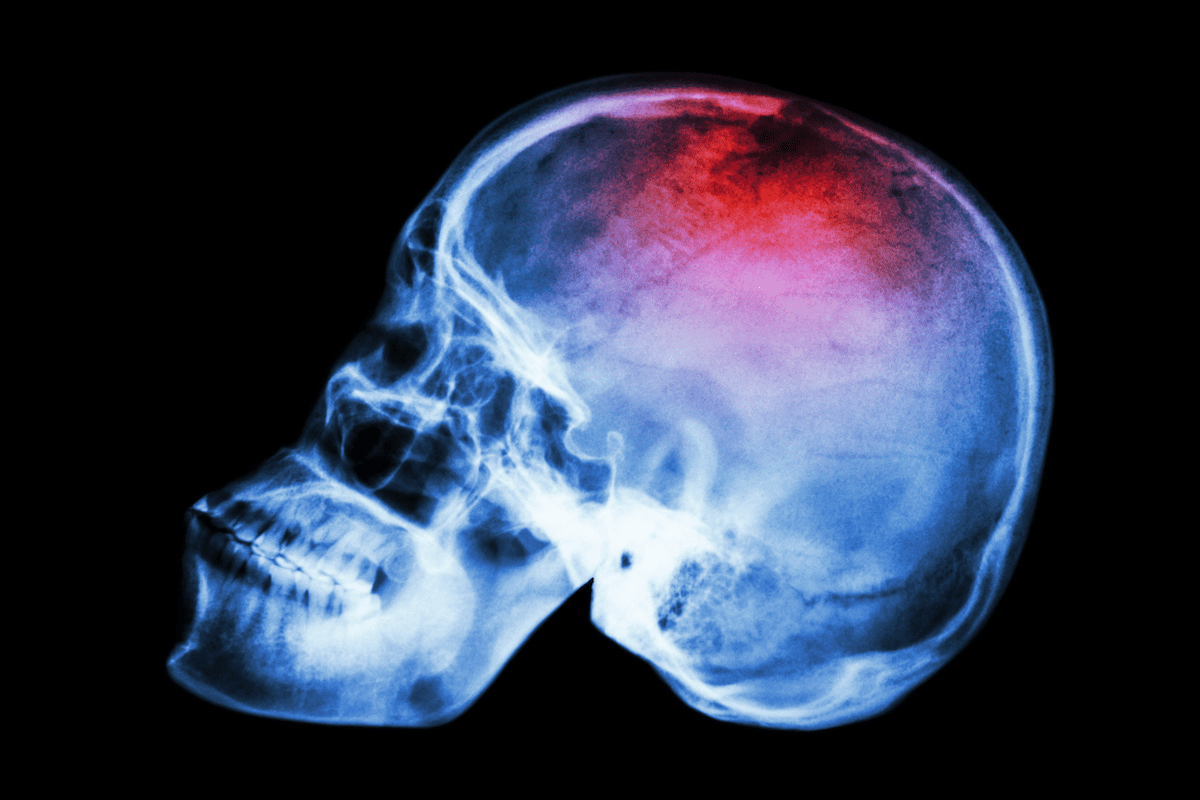

Cardiac imaging is key for finding and managing heart blockages. We use tests like stress tests, CT scans, and MRI to see the heart and its blood vessels. This helps us diagnose and plan treatment.

Getting a heart blockage diagnosed early and accurately is key. It helps doctors make the right treatment plans. Cardiac imaging is a big part of this process.

Tests like nuclear stress tests and echocardiograms give detailed heart info. This info is vital for figuring out how bad heart blockages are. It helps doctors decide the best treatment.